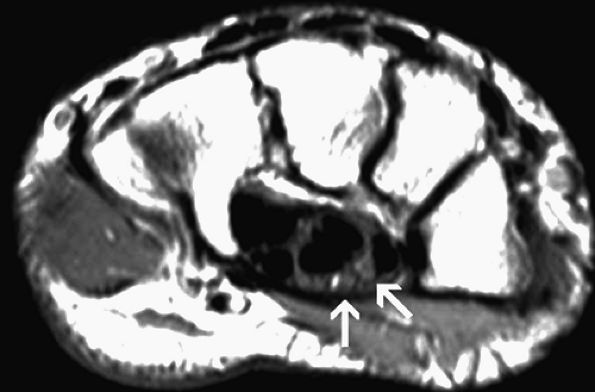

FIGURE 12.41 ● Carpal tunnel syndrome and rheumatoid arthritis. (A) Axial fat-suppressed T2-weighted image at the level of the proximal carpal row shows swelling and edema of the median nerve (white arrow) associated with flexor tendinosis (arrowheads), erosive changes (black arrow), and extensive inflammatory pannus (asterisks). (B) Axial fat-suppressed T2-weighted image at the level of the hook of the hamate demonstrates denervation edema of the thenar muscles (asterisk).

|